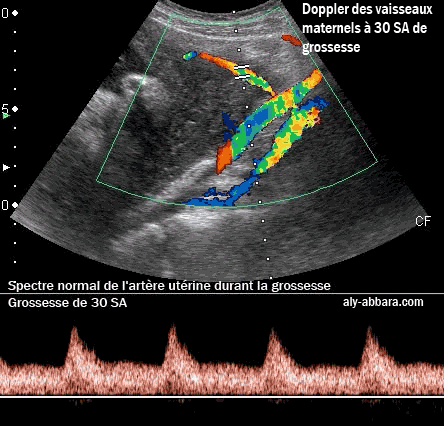

Doppler vasculaire maternel au cours de la grossesse

Image comparant les spectres du Doppler de l'artère utérine, de l'artère et la veine iliaques externes

(et non internes comme c'est indiqué sur l'image)